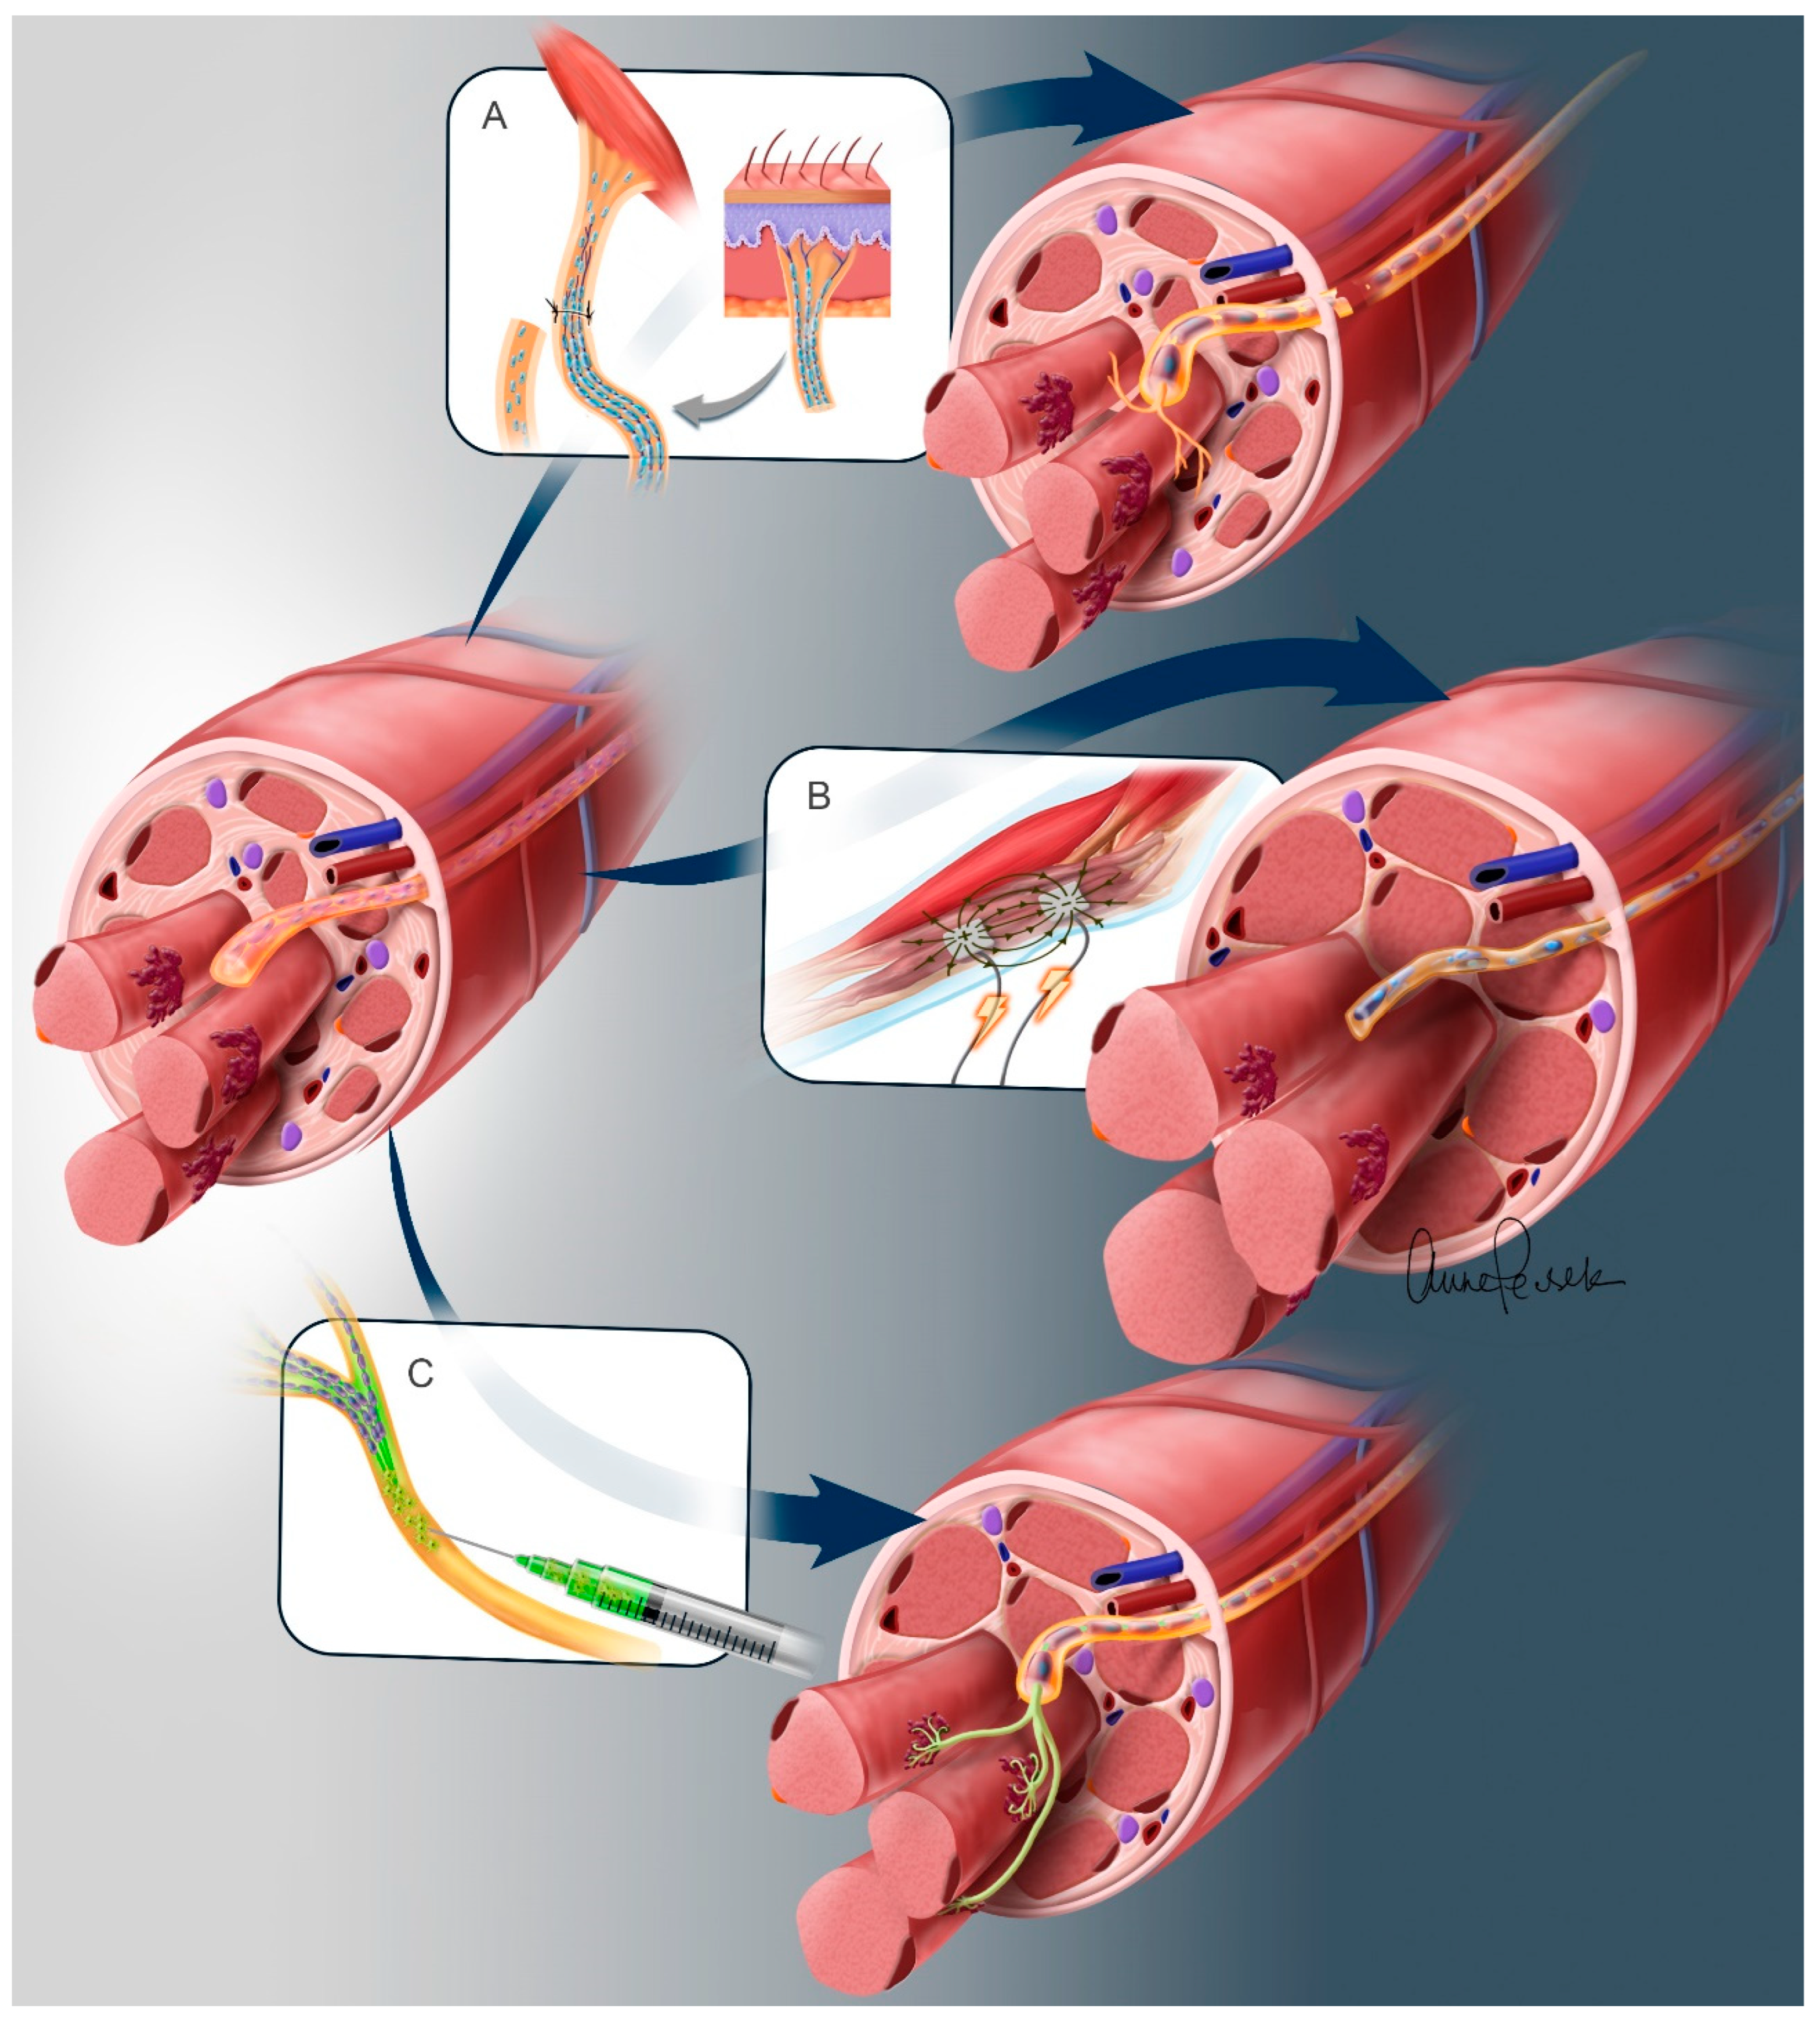

3.1. Nerve Transfers

Sensory Preservation

3.2. Spinal Motor Neuron Transplantation

3.3. Electrical Stimulation of Denervated Muscles